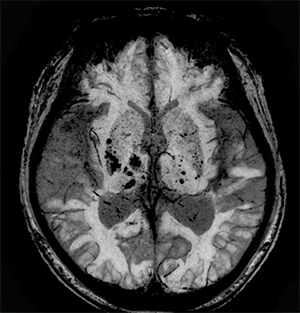

磁化率強調画像であるFSBBでは,MPGパルスの印加強度を位相・周波数・スライス方向など別々に制御可能とし,さらに,位相画像を用いた強調処理や位相画像のみの出力も可能とした。これにより,細かな血管や磁化率の変化をより詳細に捉えることができる(図1)。

図1